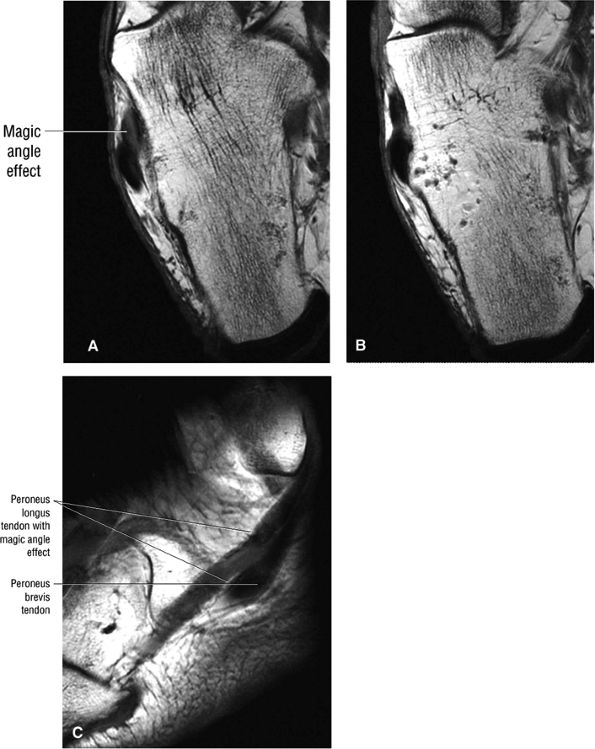

FIGURE 5.89 ● Increased signal intensity involving the peroneus longus tendon just proximal to the peroneal tubercle. This apparent signal intensity increase occurs when the orientation of the collagen fibers in the tendon approximates the magic angle of 55° with the main magnetic vector. T1, PD, and GRE sequences that use a short TE (typically <30 msec, often 10–20 msec) are susceptible to this effect. T2-weighted and FS PD FSE images with longer TE values minimize the magic-angle effect. The normal hypointense peroneus longus is seen at the level of the peroneal tubercle in B. (A, B) Axial T1-weighted images. (C) Sagittal T1-weighted image.

|